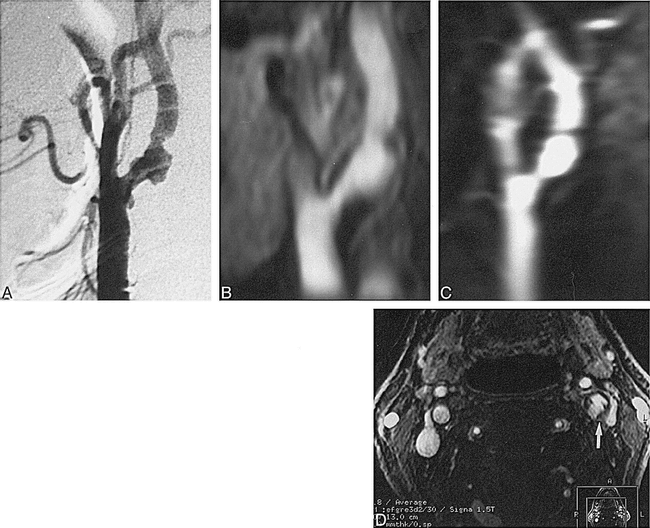

Marked thickening of left common carotid wall in a 35-year-old woman with arteritis.

A, First-pass (coronal) 3D contrast-enhanced MR angiography shows occlusion of the left common carotid artery (arrow) and the left subclavian artery. The right common and internal carotid arteries are dilated.

B, Source image of second-phase (axial) MR angiography shows marked thickening and enhancement of the wall of the common carotid artery (arrows).